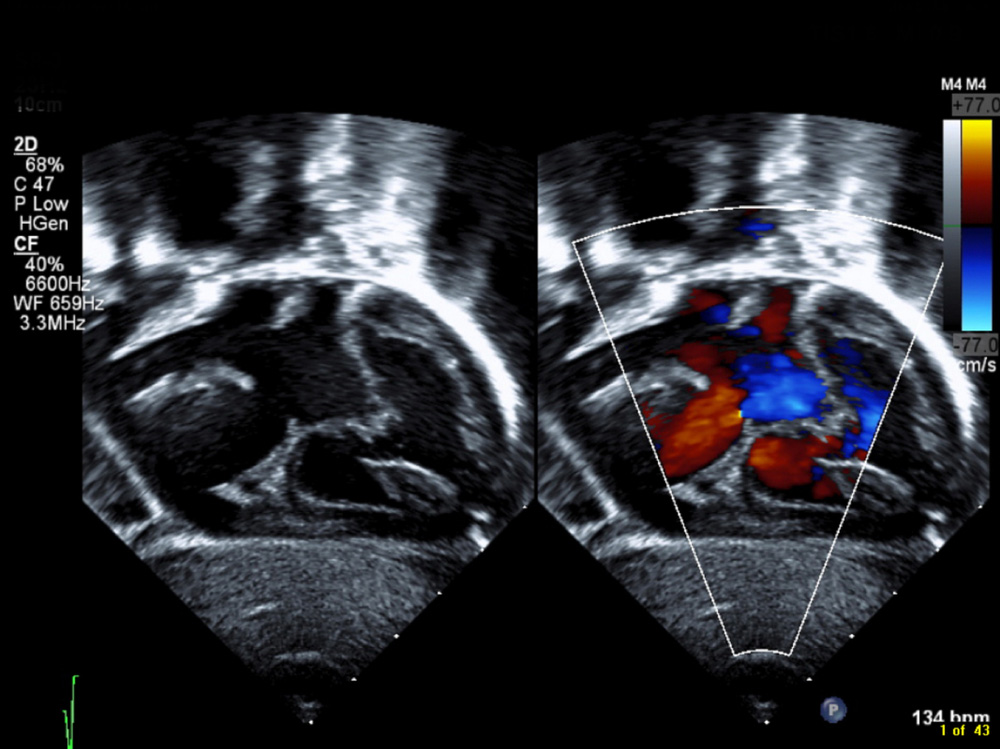

- Echocardiogram (Echo): An ultrasound of the heart that verifies the presence and size of the defect.